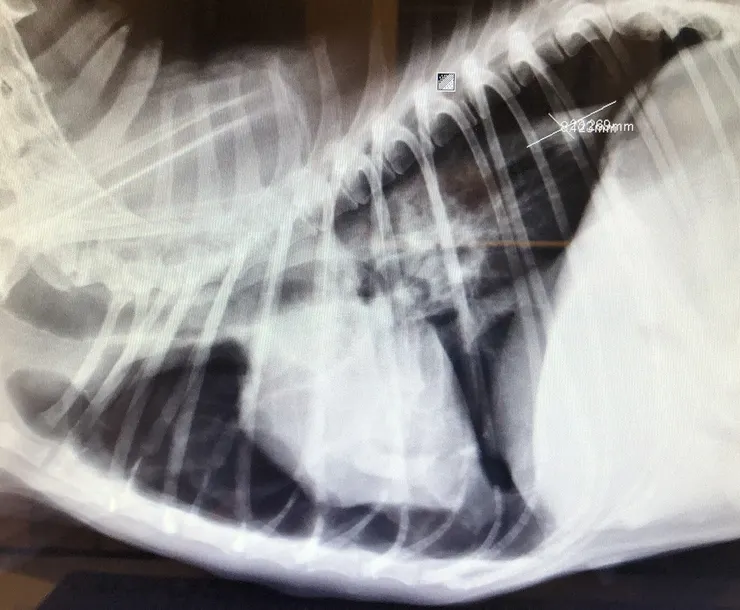

術後隔天發現灌食會返流,照X光發現巨食道,另外肝臟採樣送檢後的結果是HCC。

兩三個月後O突然帶P回診,想當然爾又P回到了DKA & collapse的狀態,除此之外P的呼吸模式非常異常,X光照下去發現左肺壓力性氣胸全都塌了,為什麼呢?

因為有塊穿破食道的骨頭。

因大氣壓力遠高於肺內的壓力,硬物穿破食道後,每一次呼吸都會使空氣從破洞灌進胸膜腔裡(肺和胸壁的空間),這時原本應充滿空氣的肺會被大氣壓力擠扁,就像皺縮的氣球一樣,而塌陷皺縮的肺是沒辦法進行氣體交換的